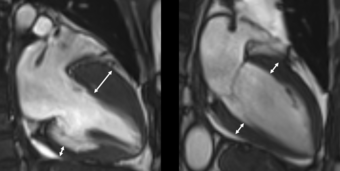

▲(사진자료) 비후성 심근병증을 가진 환자의 자기공명영상(왼쪽). 좌심실전벽의 두께가 심실 후벽에 비해 현저히

두껍다. 정상 심장 자기공명영상(오른쪽)의 경우 좌심실 전벽과 후벽의 두께가 동일하다.